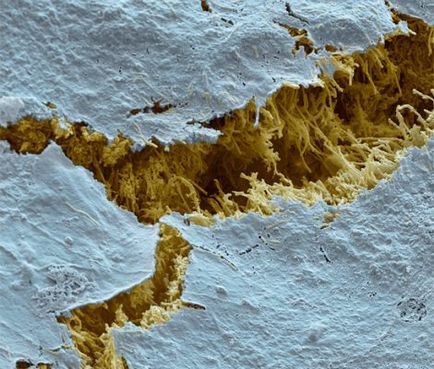

Sérült fogzománcot a mikroszkóp alatt

Mechanikai sérülés tönkre zománc